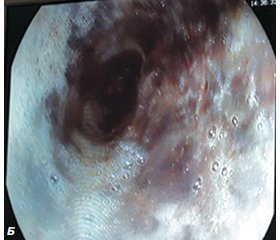

ЕГДС є одним із найбільш інформативних методів діагностики ПС [7, 11]. ЕГДС показана всім хворим із підозрою на ПС. Недоліками даного методу вважають можливість збільшення перфоративного отвору стравоходу і наростання медіастинальної емфіземи за рахунок нагнітання повітря при проведенні обстеження [5, 9]. Проте ми не відмічали суттєвого збільшення розмірів перфорації чи медіастинальної емфіземи. ЕГДС нами проведена у 24 (85,7 %) хворих із підозрінням на ПС. ЕГДС не проводили хворим, у яких факт ПС був чітко діагностований при проведенні рентгенконтрастного методу обстеження. Особливо доцільно використання ЕГДС у сумнівних випадках, у яких при проведенні рентгенконтрастного обстеження стравоходу не виявлено місця перфорації. При огляді виявляли стан слизової, наявність дефектів та їх характеристики — розміри, локалізація, краї дефекту, глибина; наявність сторонніх тіл стравоходу або ознак попереднього їх перебування — пролежні, зміни слизової. При проведенні ЕГДС виявити ПС вдалося лише у 15 (62,5 %) хворих (рис. 1).

На рис. 1А при проведенні ЕГДС виявлено спонтанний розрив правої стінки нижньої третини стравоходу розміром 5 ´ 2 см (синдром Бурхаве) із гнійним ураженням клітковини середостіння. На рис. 1Б у цього ж хворого виявлено «чорний» стравохід внаслідок тривалого блювання, що призвело до некротичних змін слизової стравоходу.